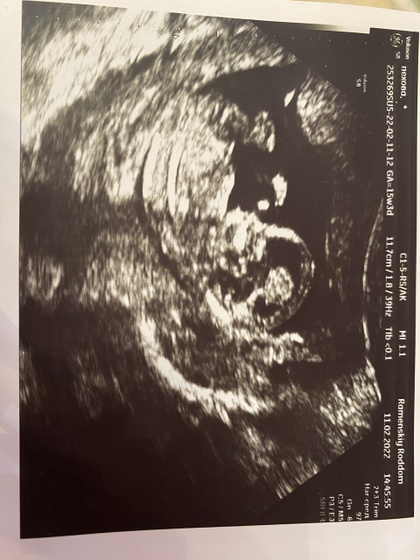

Потом все таки с опозданием я попала на скрининг. Была старенькая бабуля которая работает уже сто лет и видела обоих моих девчонок еще в животе. Сказала что все хорошо, малыш нам махал а потом сосал пальчик так мило?и даже распечатала мне снимок и 3Д я сфотографировала на телефон.

Как же я рада что всё хорошо))). И скоро я стану мамой еще одного маленького чуда????